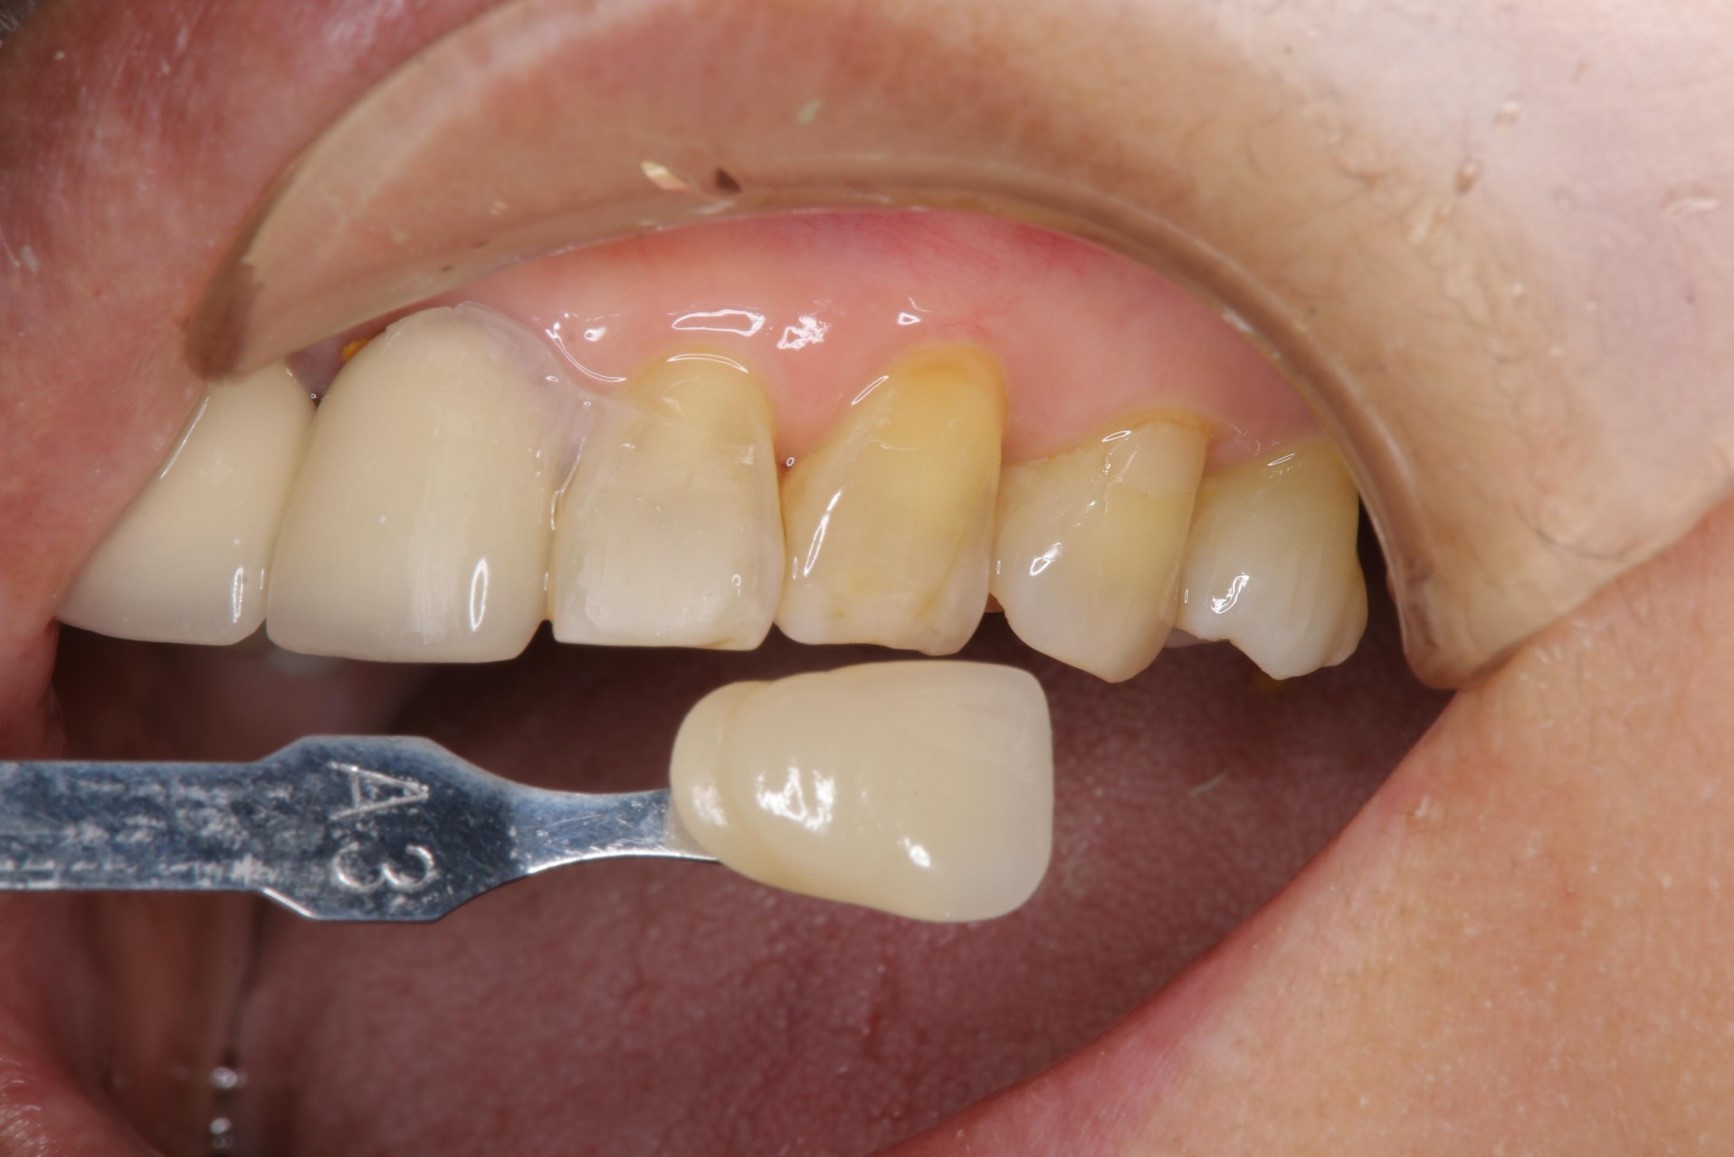

照相比色